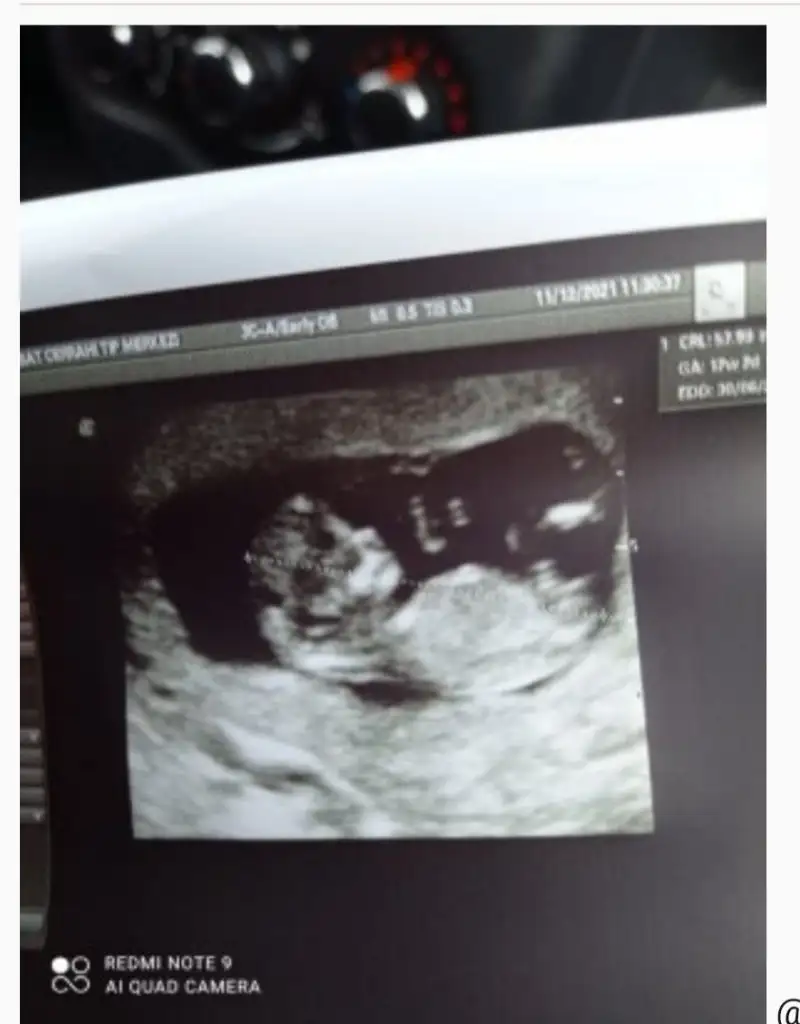

Bebeğimin cinsiyeti ...

Canim bak buraya basınca direk o mesaja gidiyorsun ultrason kagadini bulamadım galeride yoktu o yüzden bu şekilde yaptım tekrardan kusura bakma ugrastirdim seni🥰 -C-A-N-A-N- -C-A-N-A-N-